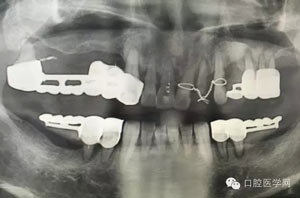

做根管的,都想做些難度大一點的,彎曲根管了、斷針了,可是臨床上很多時候是中等及以下難度的居多,我們要做的是盡我們所能做好這一部分,將我們力所能及的做好,而不是不切實際的幻想做一些我們條件設備不夠的病例。有些時候看到一些病例,很難想象是我們同行做的,我們是人,而不是神,我們也需要生活,我們追求效益沒有錯,我們給患者推薦好的材料,最終受益多的還是患者,這沒有錯,但是我們不是賣產品的,我們的本質是醫療,不是流水線上的工人,將商品加工賣出去,我們所做的一切都是建立在符合修復設計原則的基礎上的,如若不符合,我們做的再美觀,再便宜,那又有什么意義呢?無論我們做什么樣子的修復體或者是治療,我們的標準是一致的,教科書上有明確的規定,我們這社會也有畸形,就拿簡單的冠修復來說,我們花費的精力是差不多的,我們需要的步驟是一樣的,但是價格差別那么大,是我們自己制定價格的問題,還是社會的問題?如若我們的冠的價格的制定差別不大,我們將更多的心思放到醫療本身上面,那么最終受益的還是患者,可是現在是顛倒的,我們成了產品的推銷者,整天想著怎么樣將價格高的冠賣給患者,而忽略了提高學習我們自身專業能力,我們整天想著怎么樣將環境打造的多么的好,然而材料上面卻是怎么樣的省怎么來,什么便宜用什么,裝修上面我們可以花很多,材料我們卻很摳,有時候我們材料買很好,可是我們卻束之高閣,很多時候我們講理念,講概念,可是我們卻很少腳踏實地的去做我們的專業,只是用這些新鮮的名詞去和患者溝通。給大家看幾張不良的修復設計。

20.jpg

21.jpg

22.jpg

23.jpg